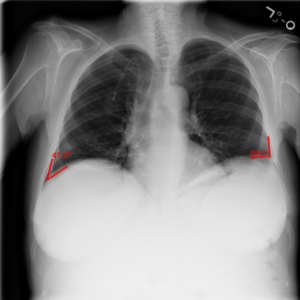

胸部画像所見の見方 | ヘルスノート。X線診断の基礎知識|胸部写真の読み方|太田東こども&おとな。胸のレントゲン写真で心臓の大きさを測ってみよう! – みどり。実践的症例レビューを通じて胸部画像診断を習得できる書籍です。- タイトル: 胸部の画像診断- 英語タイトル: Thoracic Imaging- 編者: 高橋和人- 内容: 実践的症例レビューご覧いただきありがとうございます。。胸部レントゲンについて 心胸郭比(CTR : Cardio-Thoracic Ratio。

• 胸部画像所見の見方 | ヘルスノート

• X線診断の基礎知識|胸部写真の読み方|太田東こども&おとな

• 胸のレントゲン写真で心臓の大きさを測ってみよう! – みどり

• 胸部レントゲンについて 心胸郭比(CTR : Cardio-Thoracic Ratio